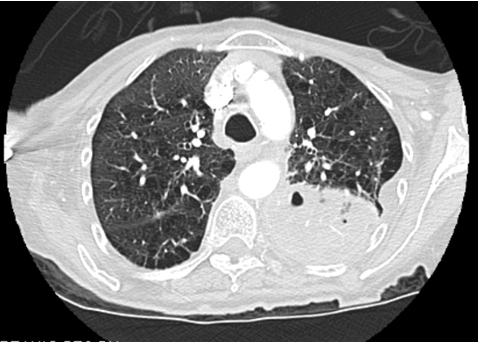

A 77-year-old female, with a 30-pack year smoking history and current 1/2 pack per day smoker, presented to the emergency department with progressive shortness of breath and hemoptysis. The patient had seen her primary care provider one week prior to arrival and was advised to have a computed tomography scan of the chest, which showed 8x4.6x10.4 cm cystic/necrotic septated mass in the left posterior mediastinum. There was also mass effect of adjacent structures including the left lower pulmonary vein which demonstrated a thrombus within the lumen (Figure 1) (Figure 2). She was started on apixaban for this questionable tumor extension versus bland clot. Hemoptysis had become significantly heavier since starting Eliquis, so she came to the emergency department for further evaluation.

Figure 1: Chest X-ray demonstrating a large mass in the left posterior mediastinum.